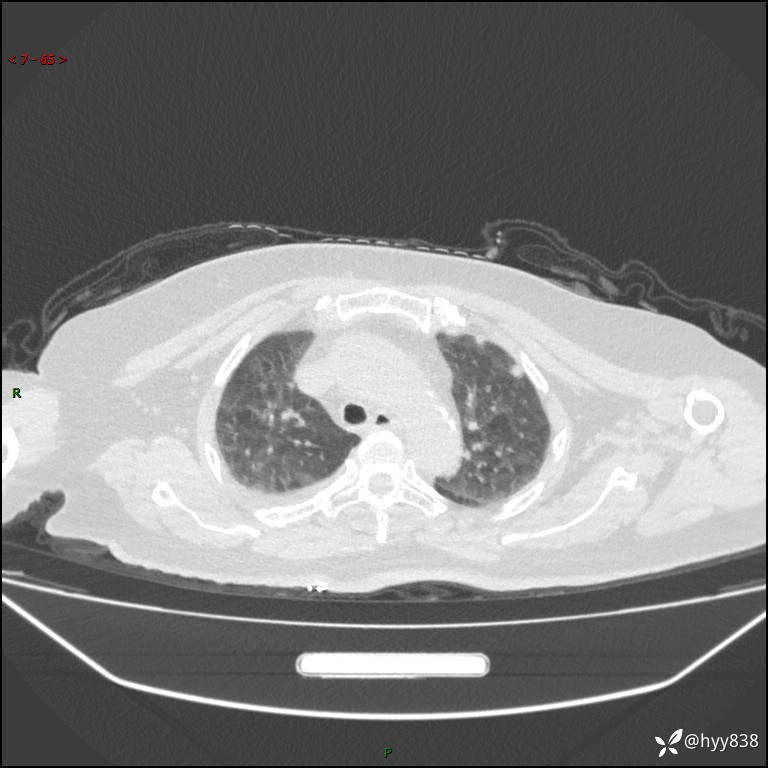

胸部 CT平扫、

颅脑MRI(T2WI+DWI)